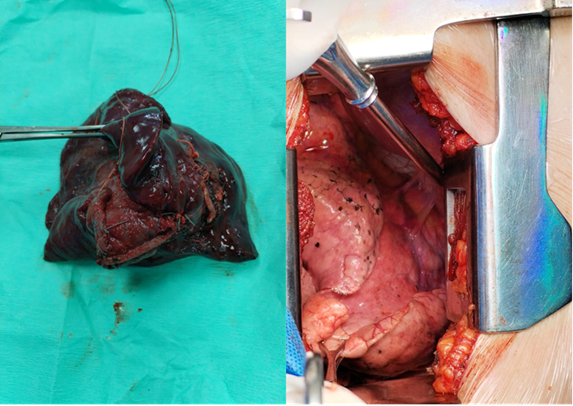

Intervención quirúrgica (mayo 2024). La paciente ingresó al Servicio de Cirugía de Tórax del Hospital Nacional Guillermo Almenara Irigoyen para manejo definitivo. Se realizó una lobectomía inferior derecha por toracotomía axilar vertical, accediendo por el quinto espacio intercostal. Se identificó una arteria sistémica aberrante intraparenquimal con ramas originadas en el seno cardiofrénico derecho (ver figura 2 a*). Se ligaron la vena pulmonar inferior, la arteria del lóbulo inferior y el bronquio lobar, extrayéndose la pieza quirúrgica sin complicaciones intraoperatorias.

Estudio anatomopatológico. La pieza mostró pleura congestiva, parénquima antracótico con bronquiectasias, fibrosis intersticial severa, inflamación crónica moderada, atelectasia y calcificación distrófica psamomatosa. Los hallazgos fueron consistentes con secuestro pulmonar intralobar complicado (ver Figura 2a ).

Figuras 2. Intervención quirúrgica y hallazgo anatomopatológico.

Figura 2ª. Pieza quirurgica resecada, donde se evidencia cambio en la coloración del lóbulo inferior derecho y fibrosis del parenquima. 2 a* arterias aberrantes visualizadas procedente de la arteria aortica pulmonar.